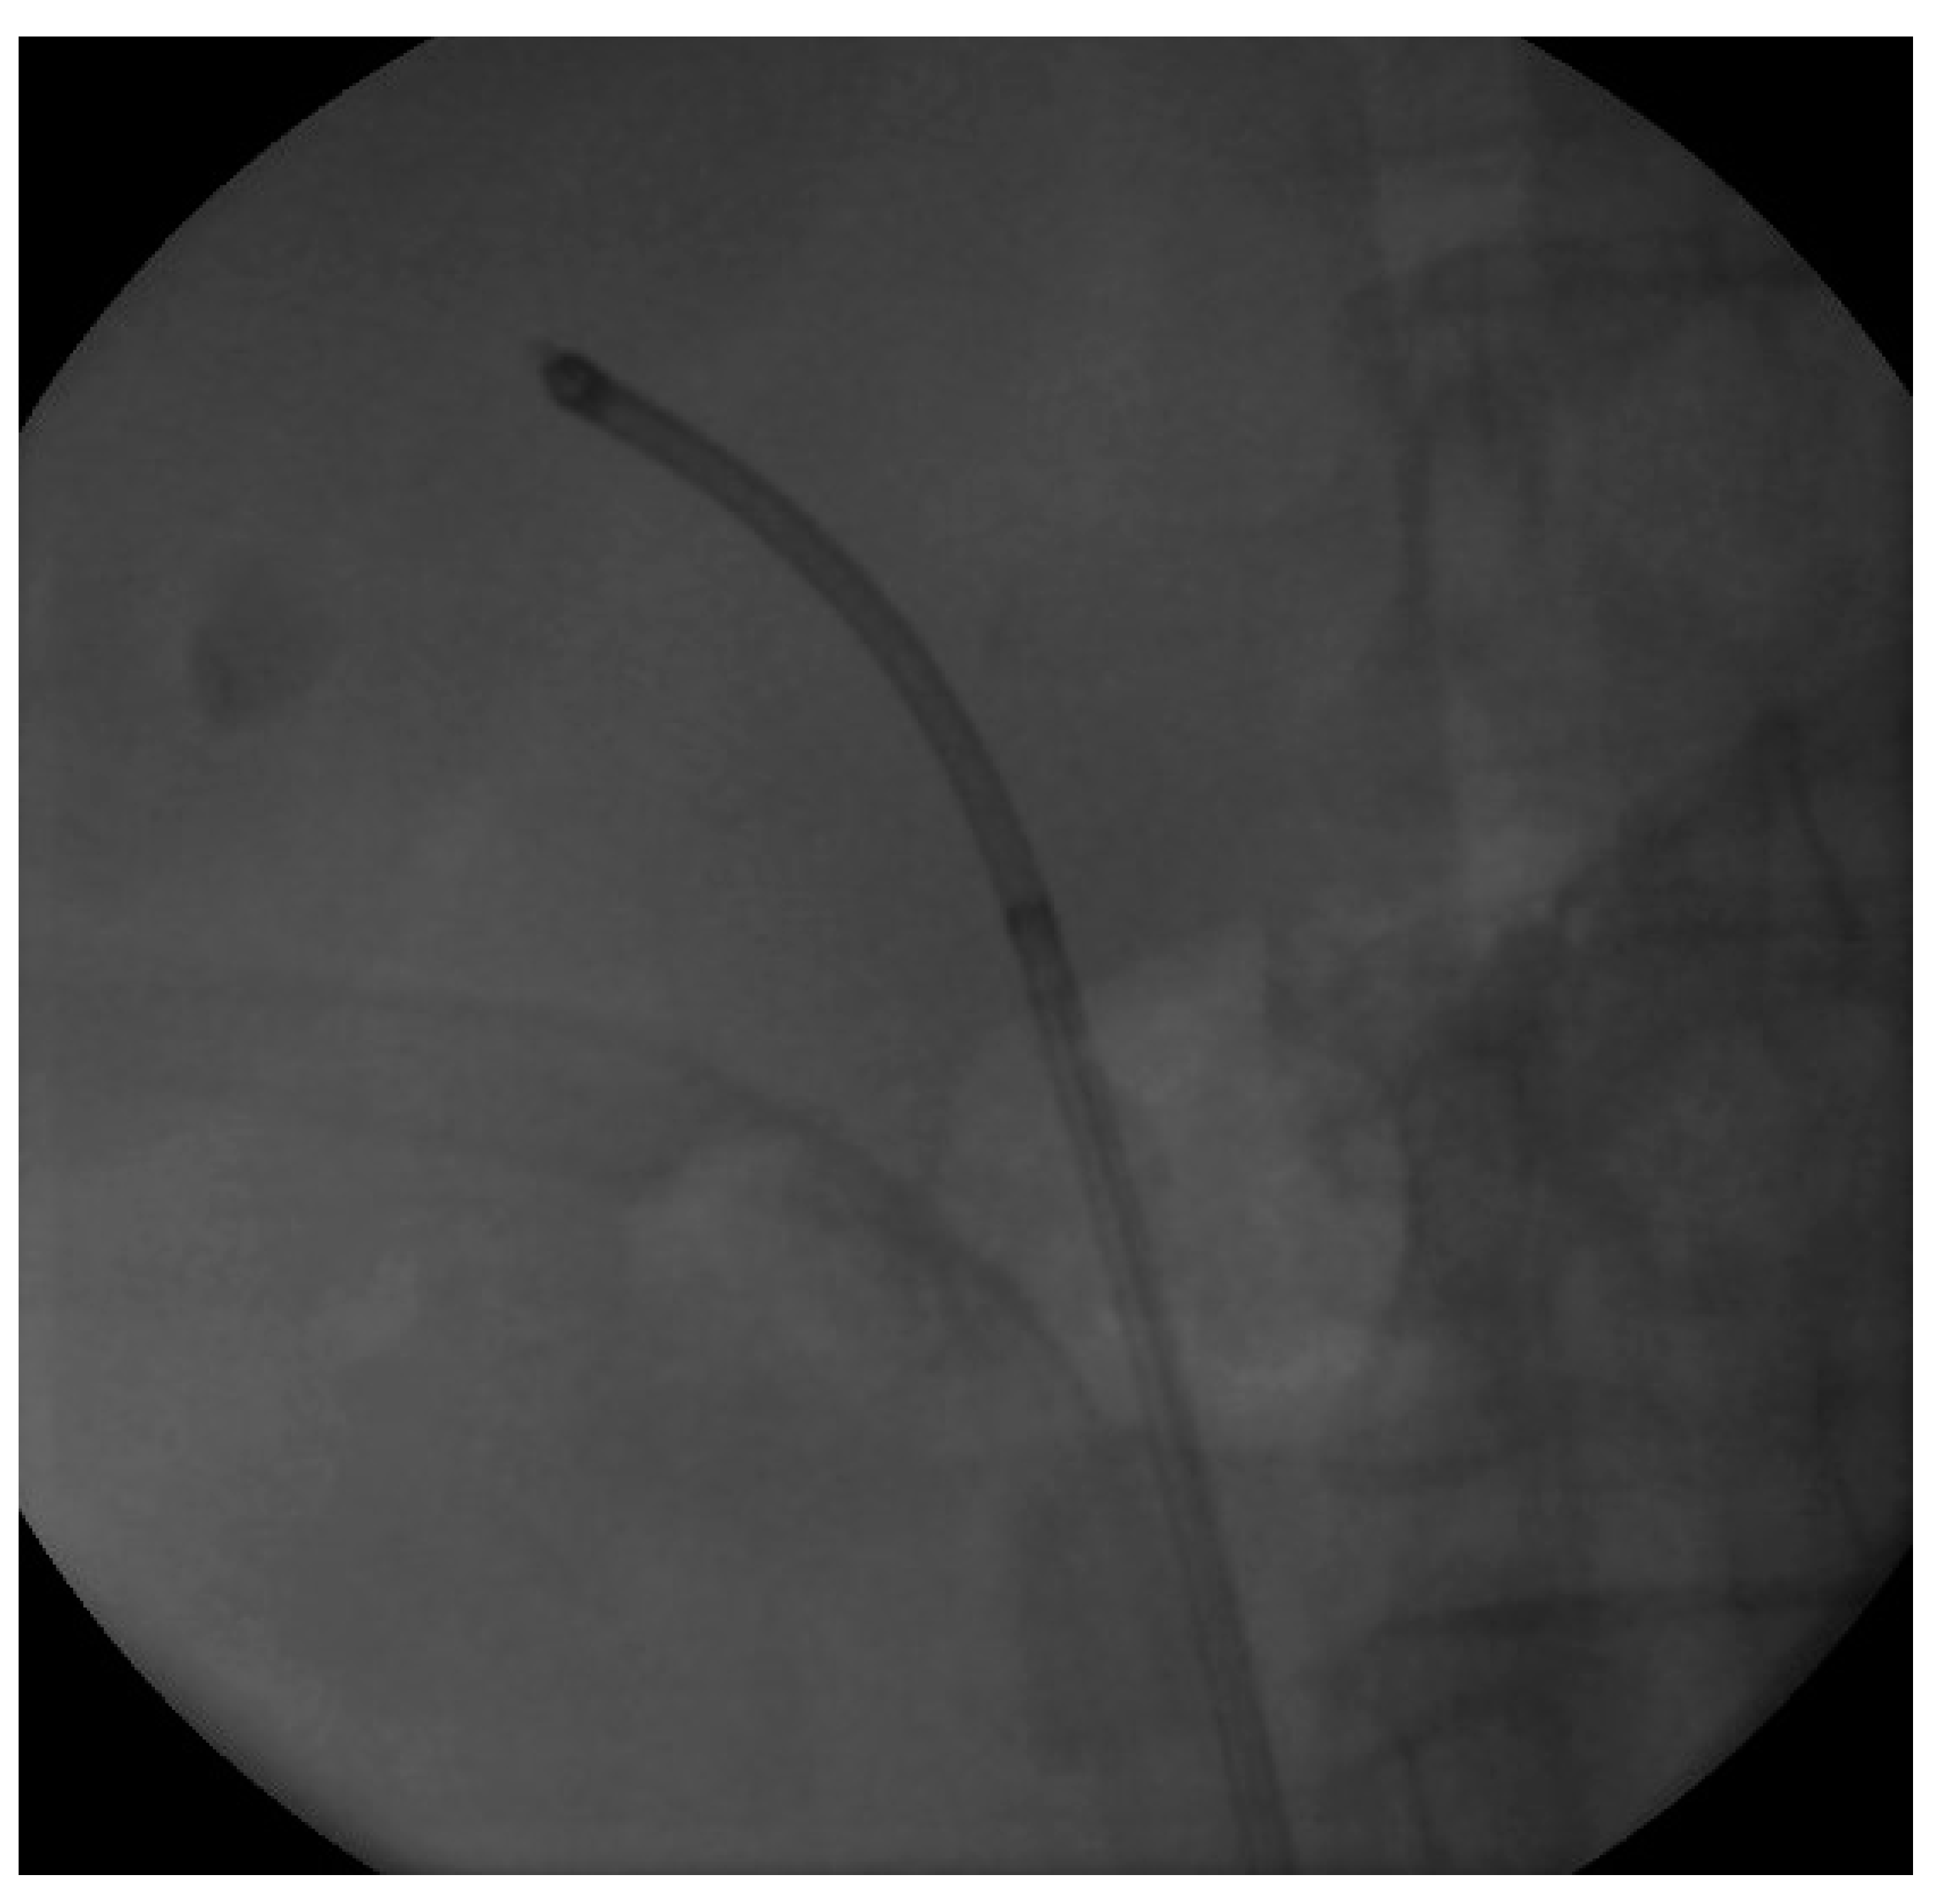

We proceeded with our standardized protocol of RIRS. Under general anesthesia, the patient was placed in the lithotomy position. At first, we performed a cystoscopy of the bladder. We found the right ureteral orifice and placed an ureteral catheter. Via the catheter, contrast agent was infused and, under fluoroscopy, the renal collecting system and the calculi was detected (Figure 1). The insertion of the guidewire followed, an ureteral access sheath was placed and through it we reached the kidney with a flexible ureteroscope of 8.6 French. The stones were found in the upper calyx and in the pelvis (Figure 2) so we began lithotripsy using holmium laser, checking throughout the whole procedure with fluoroscopy. In the meantime, the contrast agent was almost eliminated from the pelvicalyceal system and the stones were efficiently exported. Although we could not see any other calculi in the system, in the fluoroscopy there seemed to be one more (Figure 3). Therefore, we continued our endoscopy in order to find it. We came up to a small aperture in the spot that was indicated to us by the fluoroscopy, so we diagnosed an infundibulum stenosis and thought that the calculi would be within the calyx. The ureteroscope could not be inserted due to the stenosis, so we used the laser to widen the aperture. When the bore was opened and the access to the calyx was provided (Figure 4) we still could not found any calculi. In the fluoroscopy the sign has disappeared (Figure 5) so we understood that the contrast agent was entrapped in the calyx mimicking a stone in the fluoroscopy. The patient was stone free. We placed a double-J stent according to our protocol and the operation has ended. The patient the next day was free to leave the hospital without any complications, according to Clavien–Dildo system.

Figure 4. The calyx after the widening of the infundibulum.